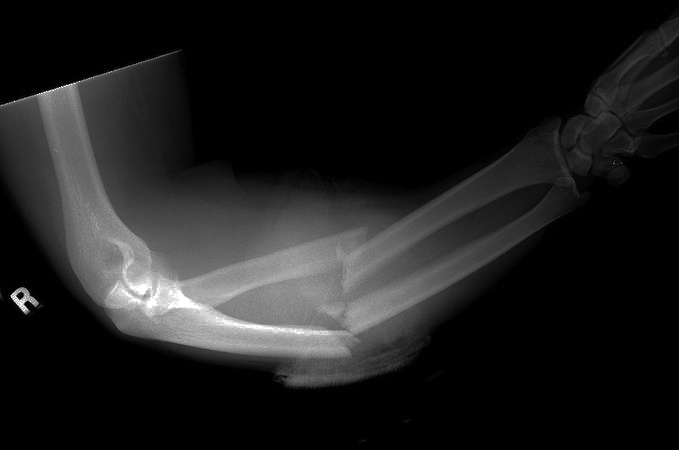

- A Monteggia fracture involves a fracture of the proximal third of the ulna combined with a subluxation or dislocation of the radial head at the PRUJ and the humeroradial joint.4,8

- These injuries most commonly occur secondary to a direct blow to the posterior aspect of the ulna, with the elbow extended and the forearm in hyperpronation.12,13

- Monteggia fractures account for <2% of all forearm fractures.12

Imaging13